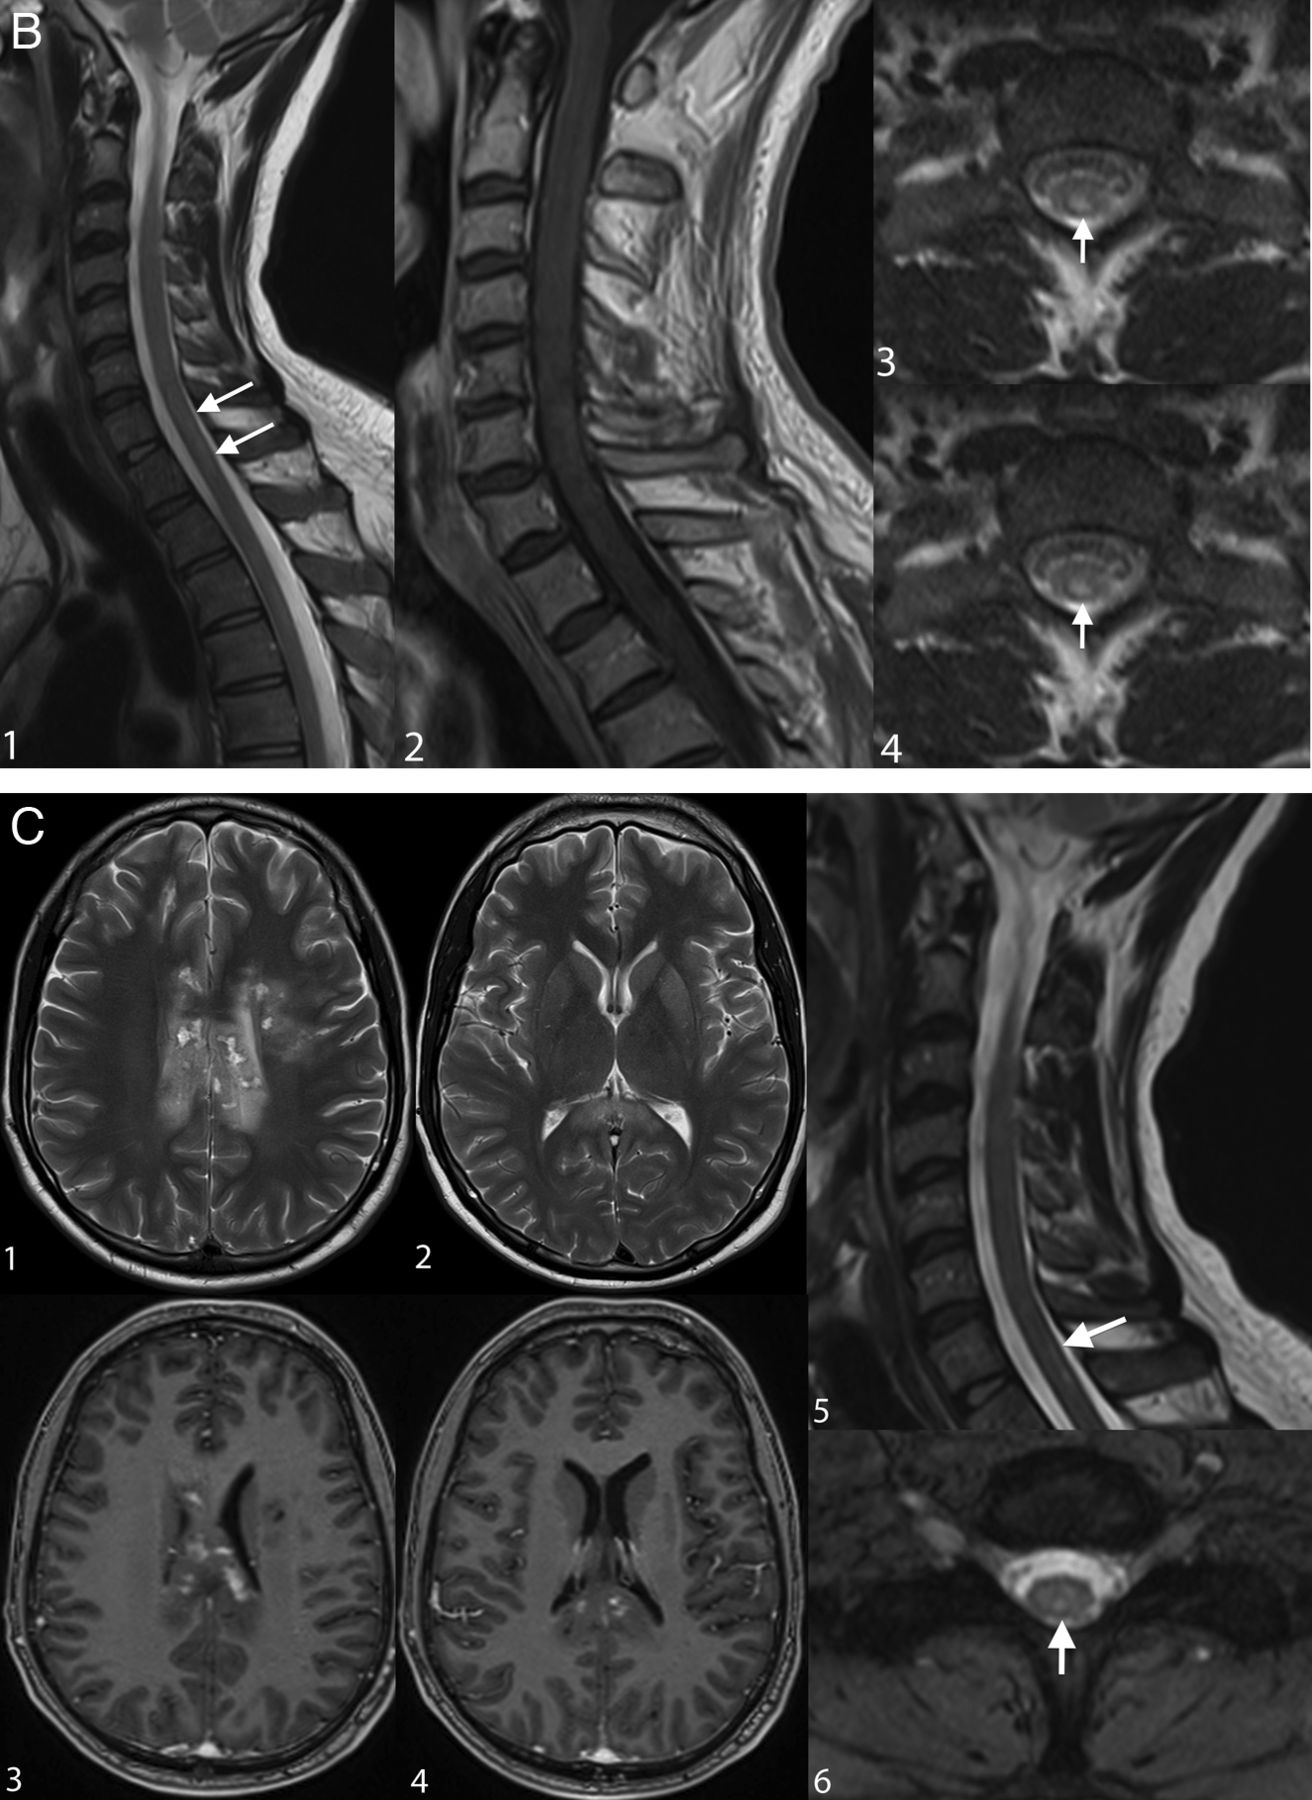

Examples of irreversible brain and spinal cord lesions due to decompression sickness (A, B, and C are taken from the same patient). A, On DWI (1, 2, 3, 4, 5, 6), the areas of restricted diffusion correspond to lesions of the corpus callosum and frontal white matter on both sides. They appear as high signal on T2WI (7, 8, 9). B, Sagittal (1 and 2, white arrows) and axial (3 and 4, white arrows) T2WI shows a cervicothoracic (C7–T1) lesion appearing as high signal without contrast enhancement on T1WI (2). C, On follow-up 1 month later, the lesions described in A and B are still present on these brain (1, 2, 3, 4) and spine (5, 6) images. Note the enhancement of the corpus callosum (3 and 4). Lesions of the right frontal deep white matter and corpus callosum have healed and now appear as “little cavities.” Similar features are usually seen in ischemic or necrotic lesions of the central nervous system.